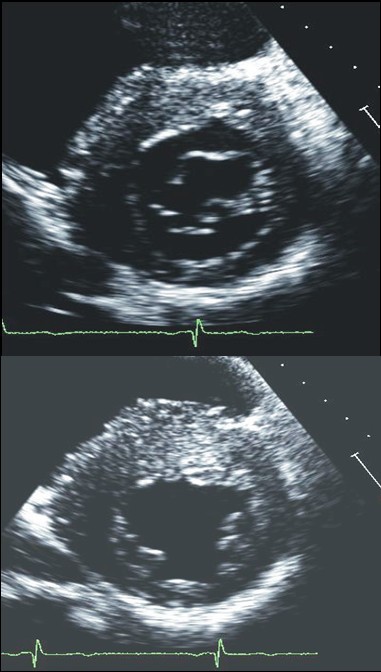

Figure 3From: Echocardiography in patients with hypertrophic cardiomyopathy: usefulness of old and new techniques in the diagnosis and pathophysiological assessment Examples of patients with hypertrophic cardiomyopathy with typical asymmetrical left ventricular hypertrophy.Back to article page